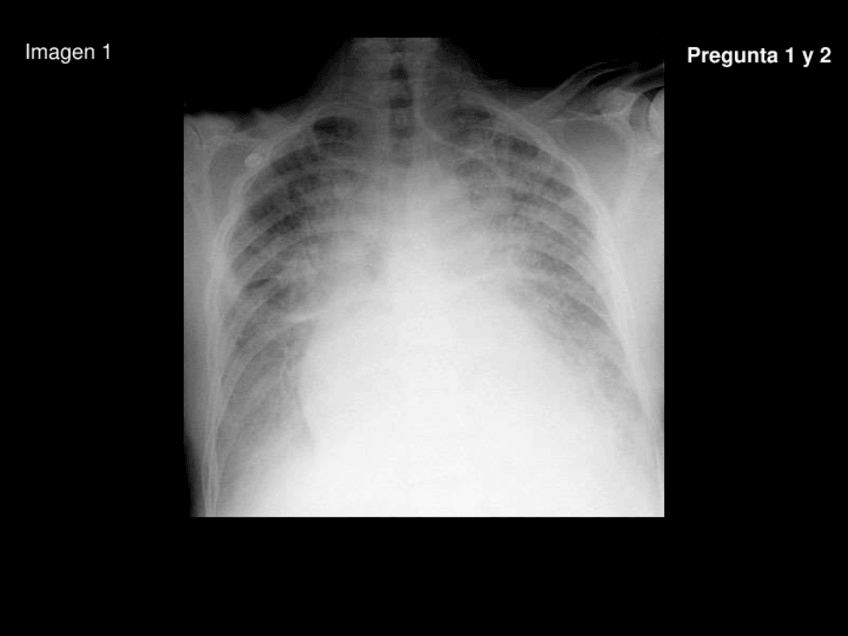

Exámenes - Preguntas-de-rayos-resueltas.pdf

13 páginas